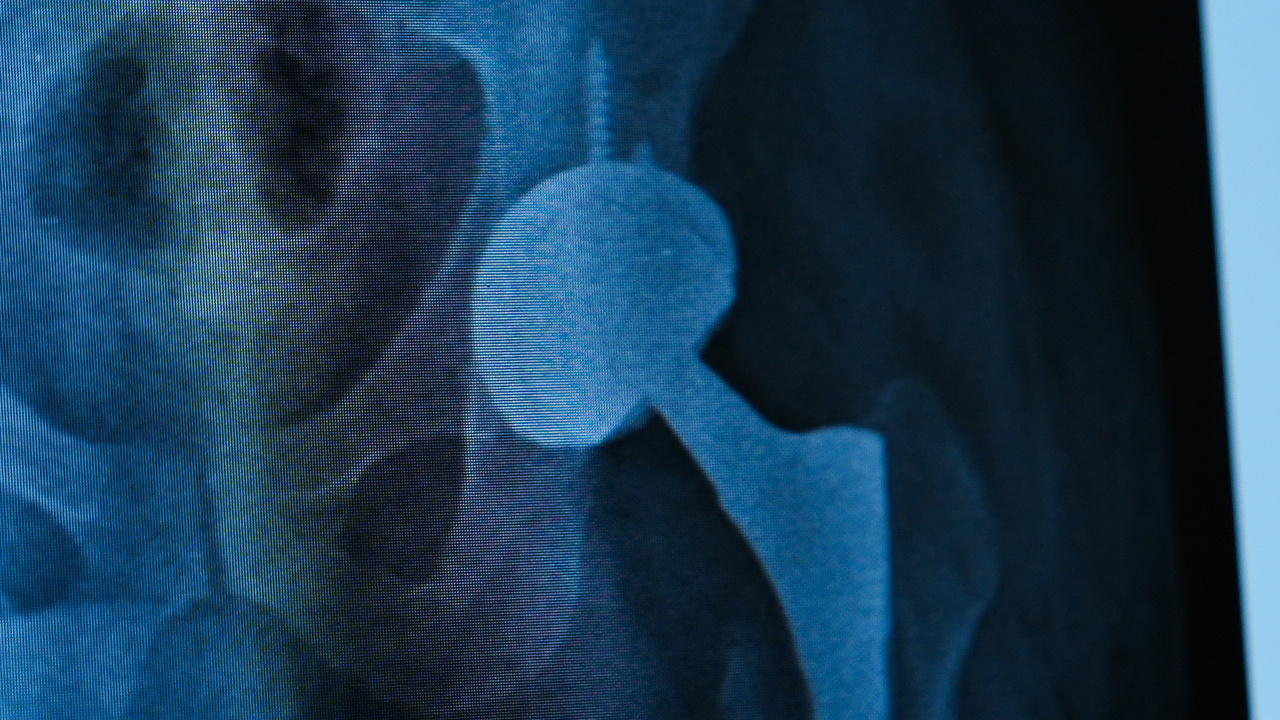

Kalça protezi ameliyatından sonra meydana gelen enfeksiyon nedeniyle şiddetli ağrılar çeken Zafer Aygün, Medipol Sağlık Grubu’nda uygulanan tek aşamalı cerrahi yöntemi ile ağrısız bir şekilde yeniden yürümeye başladı. Ortopedi ve Travmatoloji Uzmanı Prof. Dr. İbrahim Azboy’un gerçekleştirdiği tek aşamalı protez ameliyatı ile kalça enfeksiyonu tedavi edilen Aygün, “Uzun zamandır ilk defa ağrısız yürüyorum. Hayata yeniden döndüm” dedi.